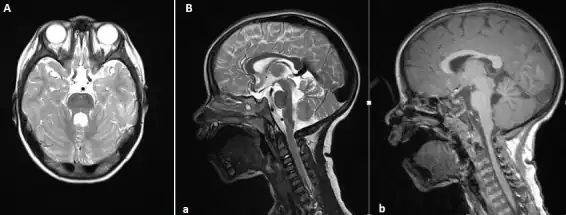

Diagnosis

The disorder is characterized by the absence or underdevelopment of the cerebellar vermis and a malformed brain stem (molar tooth sign), both of which can be visualized on a transverse view of the head MRI scan.[19] Together with this sign, the diagnosis is based on the physical symptoms and genetic testing for mutations. If the gene mutations have been identified in a family member, prenatal or carrier diagnosis can be pursued.[6]